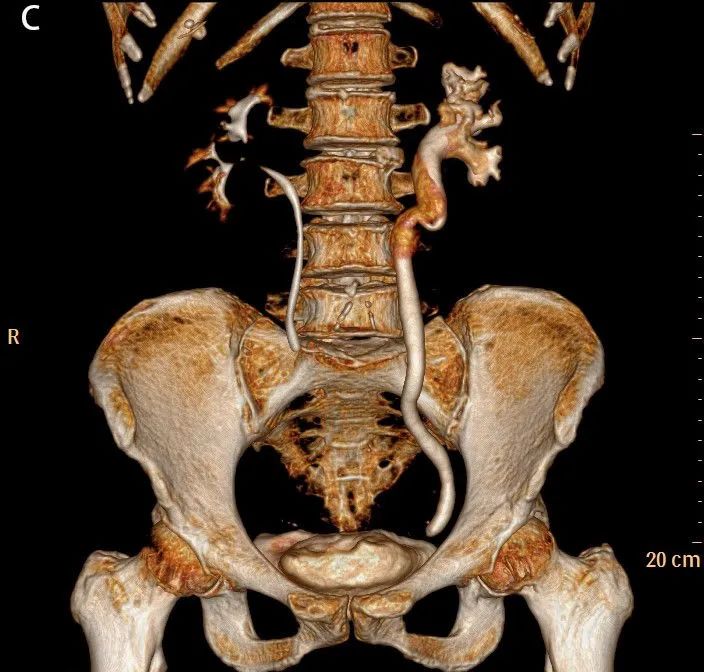

图4A

图4B

图4C

图4A-C:左侧肾盂及输尿管上段呈“双环及双腔样”改变,考虑夹层形成;三维重建可清楚的观察到撕裂肾盂及输尿管的真假腔并显示撕裂范围。